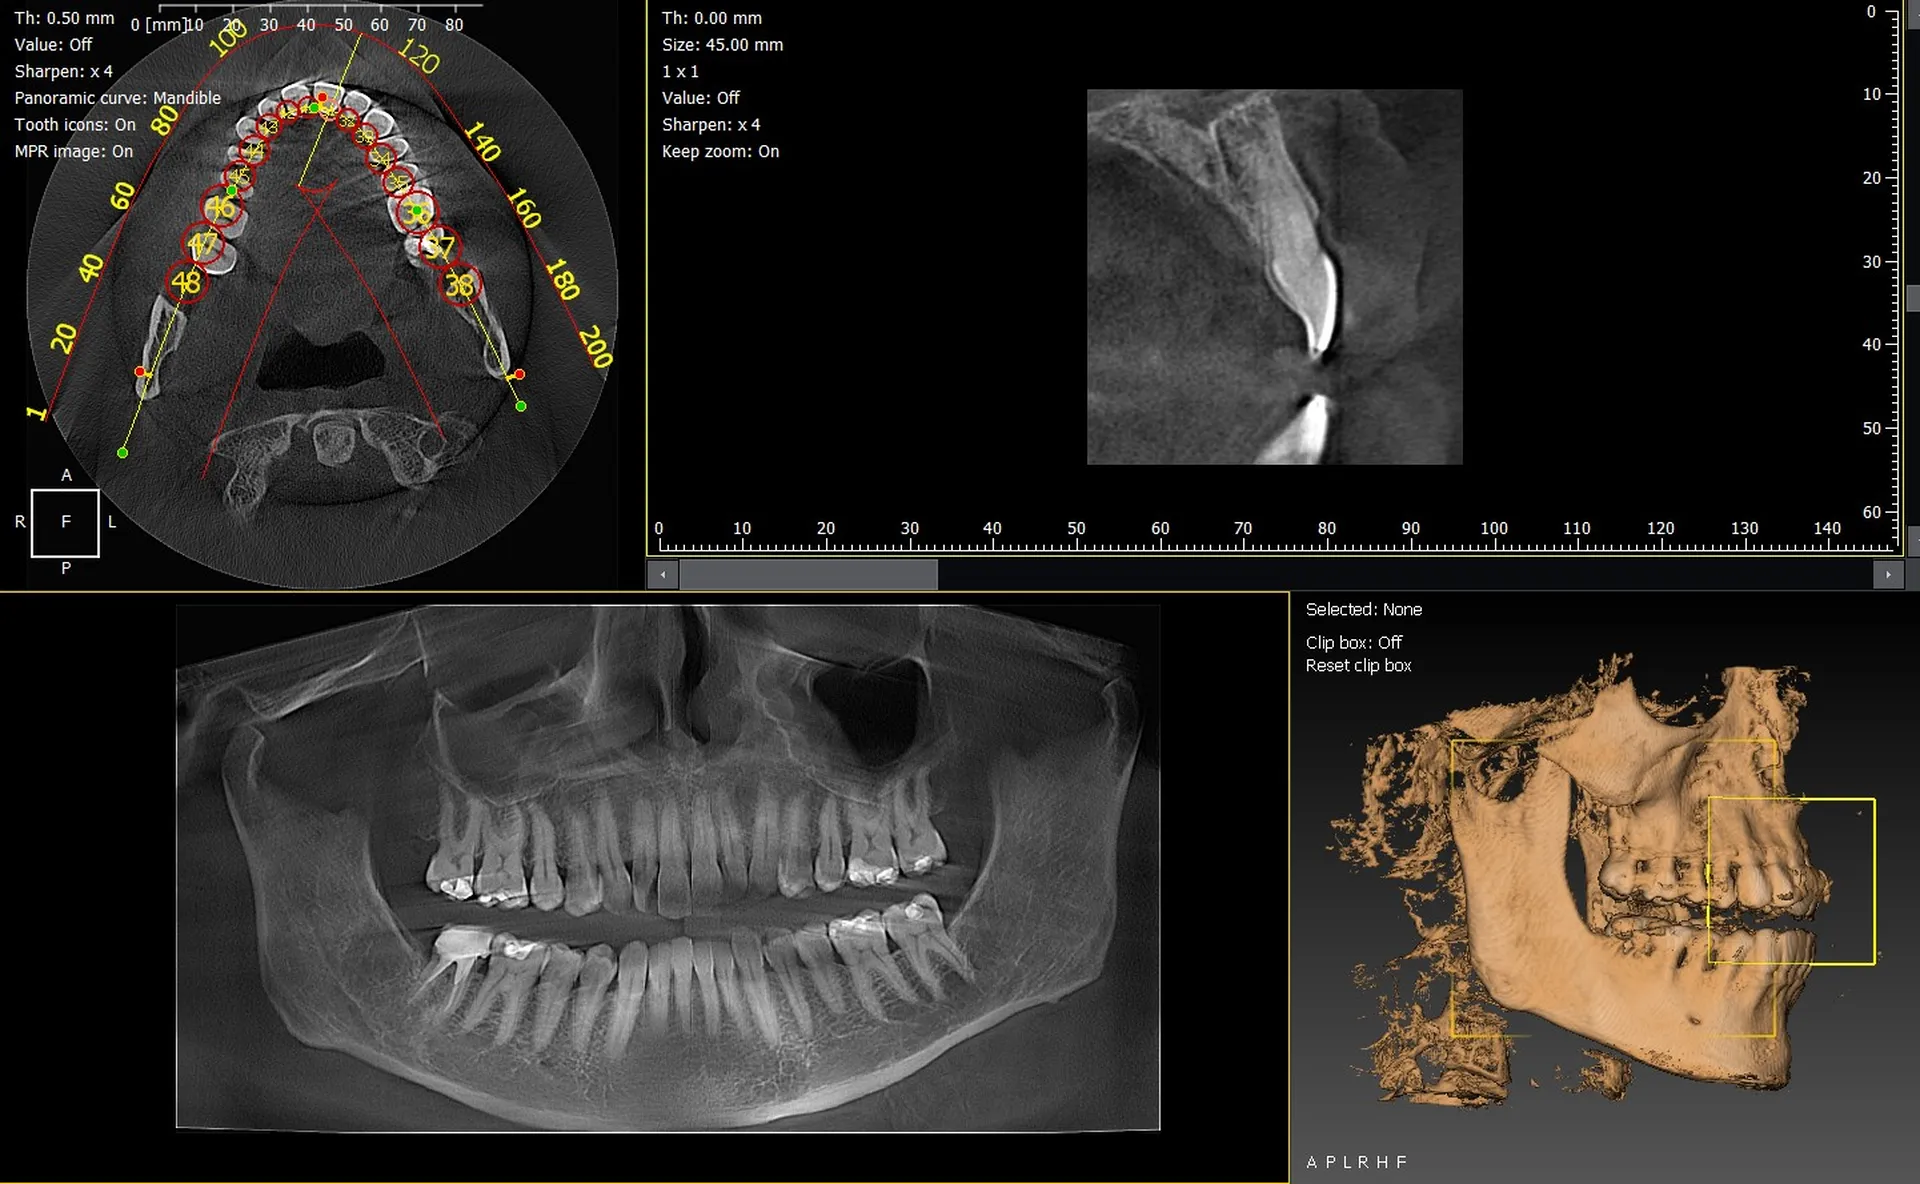

Les cabinets dentaires de Digne-les-Bains et du département des Alpes de Haute Provence 04 recherchent des solutions d’imagerie 3D performantes afin d’améliorer la précision de leurs diagnostics et de renforcer la qualité de prise en charge. Les systèmes CBCT modernes offrent une vision volumétrique essentielle en implantologie, endodontie, orthodontie ou chirurgie orale. Les modèles Dürr Dental VistaVox et Owandy I-Max 3D comptent parmi les équipements les plus fiables et les plus innovants dans le domaine.

Dürr Dental VistaVox : une imagerie 3D haute résolution pour diagnostics avancés

Le VistaVox est conçu pour répondre aux exigences cliniques les plus complexes. Son champ d’acquisition optimisé pour couvrir l’arcade complète permet une analyse détaillée du nerf mandibulaire, des sinus et des structures osseuses délicates.

Owandy I-Max 3D : une solution compacte et polyvalente pour tous les cabinets

L’Owandy I-Max 3D, appareil mural léger et ergonomique, permet aux cabinets disposant d’un espace restreint d’accéder à une imagerie panoramique et 3D de haute qualité.